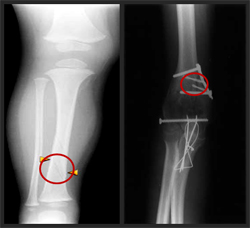

Prediction and control of bone drilling forces are critical to the success of many orthopaedic operations. Uncontrolled and large forces can cause drill-bit breakage, drill breakthrough, excessive heat generation, and mechanical damage to the bone. In this stduy, a mechanistic model was developed a mechanistic model for the bone drilling process to enable prediction of bone drilling forces as a function of drill-bit geometry and drilling conditions.

The model incorporates the radially-varying drill-bit geometry and cutting conditions analytically, while capturing the material and friction properties empirically through a specific energy formulation. The forces from the chisel edge are modeled by considering the indentation process that occurs in the vicinity of the drill-bit axis. In the drilling experiments, a micro-scale (170 µm) pilot hole was first drilled on the bone with a micro-drill to separate the chisel edge and cutting-lip forces.

A procedure is outlined to calibrate the specific energies, where only a small number of calibration experiments are required for a wide range of drilling conditions and drill-bit geometry. The calibration parameters for the cortical portions of bovine tibia are identified through drilling tests. Subsequently, a series of validation tests are conducted under different feed rates and spindle speeds. The thrust forces and torques were observed to vary considerably between bones from different animals. The forces from the model were seen to match well with those from the experimentation within the inherent variations from the bone characteristics. The model can be used to select favorable drilling conditions, to assist in robotic surgeries, and to design optimal orthopaedic drill bits.